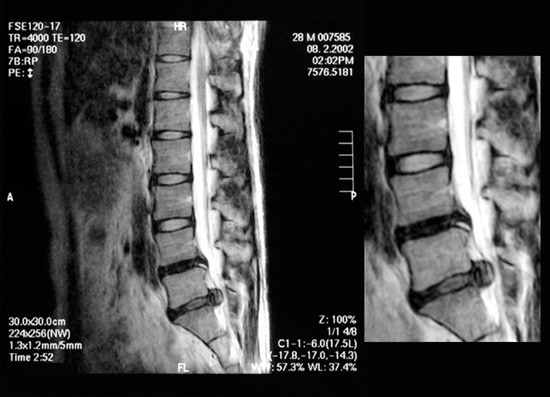

腰椎椎間板ヘルニアとは、背骨の間にあるクッションの役割を果たす椎間板が変性し、一

部が突出して神経を圧迫することで痛みやしびれを引き起こす疾患です。発生する部位に

よって名称が異なり、頚椎椎間板ヘルニア・胸椎椎間板ヘルニア・腰椎椎間板ヘルニアに

分類されます。その中でも、最も発症しやすいのが腰椎椎間板ヘルニアです。

椎間板の中心には髄核と呼ばれるゼリー状の組織があり、加齢や負荷の影響で⻲裂が生じ

ると、髄核が外に飛び出し神経を圧迫。これが痛みやしびれの主な原因となります。